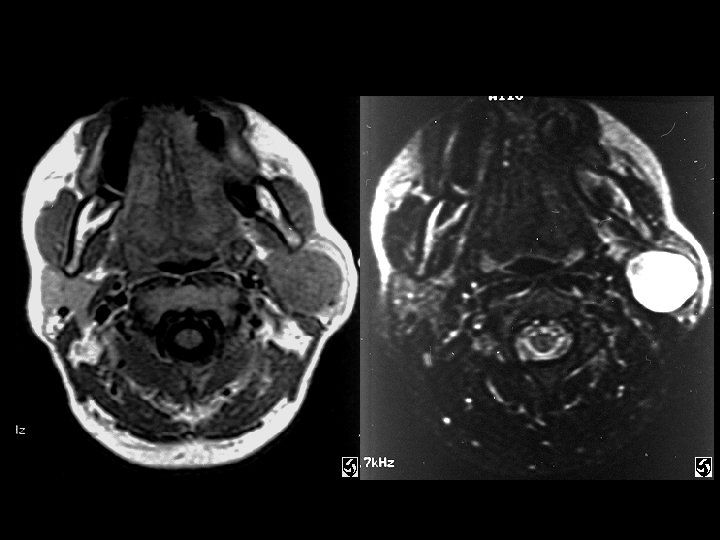

Parotid pleomorphic adenoma • Findings: – Intensely bright T 2 parotid lesion • ddx: – Adenoid cystic tumor – Mucoepidermoid – hemangioma